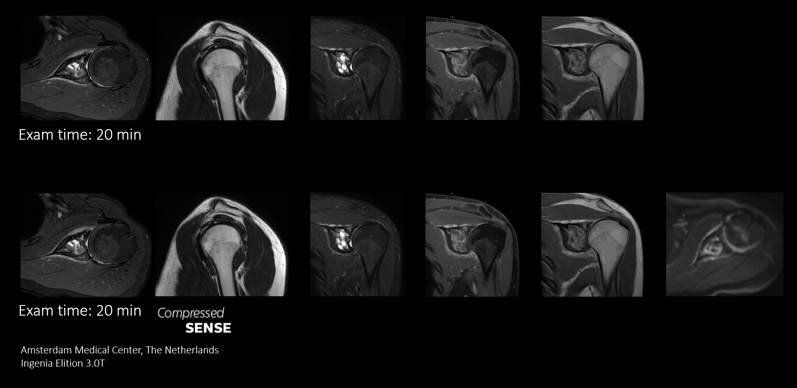

More information in the same time slot

Compressed SENSE gives MRI departments the flexibility to acquire as much relevant information as possible within the MRI scan time slot. Its speeds allows extra routine and functional sequences to be added to enhance diagnostic information.

This case demonstrates the ability to add additional sequences within the same time slot to enhance your diagnostic confidence. Besides traditional TSE sequences, you can now add a functional DWI sequence within the same timeslot, providing additional information for you to base your diagnosis on.

Because the faster scanning with Compressed SENSE saves us time, we can add a sequence to obtain high quality images for confident diagnosis."

Sachi Fukushima, Radiological Technologist, Kurashiki Central Hospital, Japan